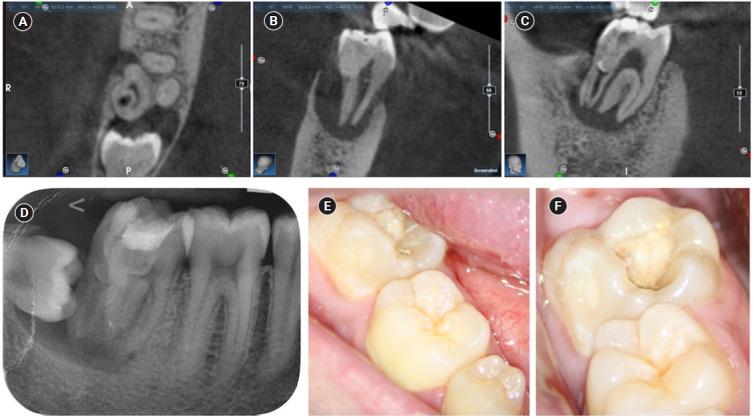

The present case report describes the endodontic treatment of a type III B dens invaginatus (DI) in a three-rooted mandibular second molar since the invagination invades the root and extends apically. Clinical and cone-beam computed tomography examination of the mandibular second molar showed a broadened coronal morphology, DI, a third root, periapical radiolucency, and compression of a distal root canal by the invagination, which developed an atypical semilunar shape. The tooth was diagnosed with pulpal necrosis, symptomatic apical, and peri-invagination periodontitis. Consequently, three-dimensional virtual reconstruction was conducted to improve anatomical interpretation and case planning and accelerate the intraoperative phase by reducing operator stress and minimizing intraoperative variables. The present case report aims to raise awareness of the existence of DI on the mandibular second molar.

摘要

本病例报告描述了一例下颌第二磨牙III型B型牙内陷(DI)的根管治疗,因为该牙内陷侵入牙根并向根尖延伸。对该下颌第二磨牙进行的临床和锥形束计算机断层扫描检查显示,其冠部形态变宽、存在牙内陷、有第三根、根尖周透射区以及牙内陷对远中根管造成压迫,形成了非典型的半月形。该牙齿被诊断为牙髓坏死、有症状的根尖周炎和牙内陷周围牙周炎。因此,进行了三维虚拟重建,以改善解剖结构解读和病例规划,并通过减轻术者压力和减少术中变量来加速手术进程。本病例报告旨在提高对下颌第二磨牙存在牙内陷情况的认识。